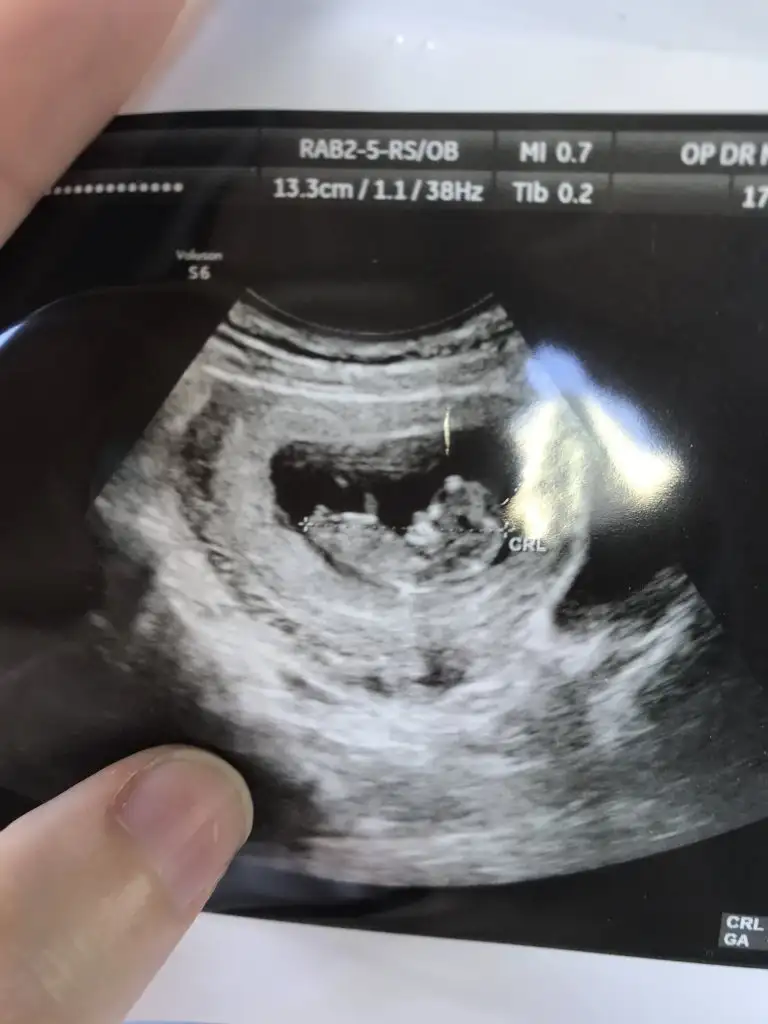

Nubu yüksek görünüyor sanki net değil karışık görünüyor emin olamadimBaşka usg yok doktor kıza benziyor demisti ama net değil demisti

Canım 11 de büyük olasılık kız 12 de nubu kalktı kız da olabilir erkek de dedi. 15 te %100 kız dedi 16 da hala kız dediSize 12.haftada doktor, erkek mi dedi?

Kız gibi sanki kaç haftalık usgler 11 12 13 haftalar olmalı

12 haftalıkKız gibi sanki kaç haftalık usgler 11 12 13 haftalar olmalı

Emin olamadım başka USG varsa paylaşın sanki erkek gibi gibi ama emin değilimMerhaba 11+0 tahminde bulunur musunuz?

Birde bu var :)Emin olamadım başka USG varsa paylaşın sanki erkek gibi gibi ama emin değilim

Net değil olursa 12 13 haftalar paylasirsinBirde bu var :)

Merhaba tahmininiz doğru çıktı doktorumuz %95 kız dediDr tam -----+ nubtan geçmiş ölçümü emin değilim sanki kız 11 12 13 haftalar olursa paylasin